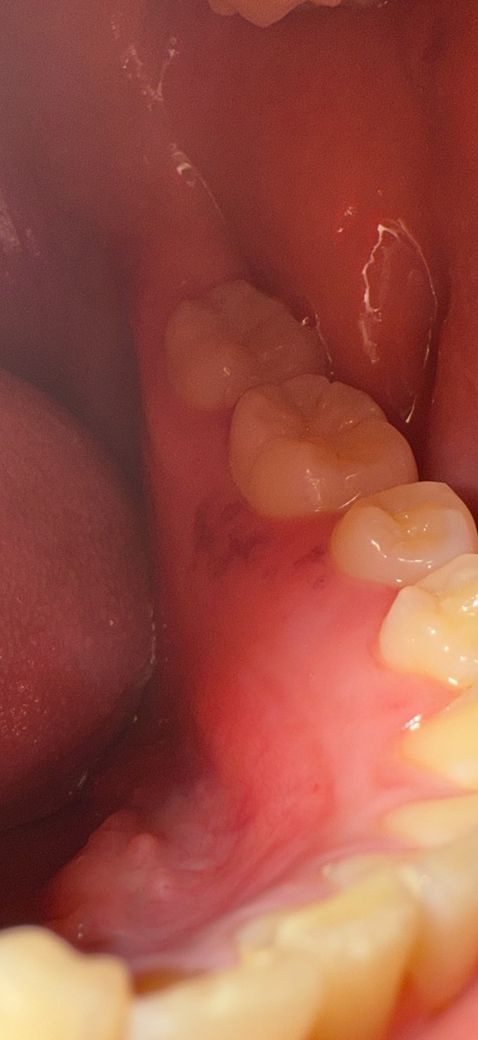

사진은 순서대로 목요일 - 금요일(어제) - 금일오전 - 금일 오후입니다. 처음엔 부어서 살이 울퉁불퉁 올라온 느낌(통증없음), 살짝 하얗게 수포처럼 올라옴 (통증 무), 염증 아문 듯한 빨간 흉터 (통증무), 오늘은 마치 긁힌? 패인? 듯한 염증자국 (혀로 건들면 정말 아주 조금 따끔)

혀로 만져보면 오늘은 실제로도 패인듯한 촉감입니다 ㅜ 네번째 사진에 허옇게 보이는 건 팝콘찌꺼기 일수도 있어요 (방금 먹고 찍었는데 억지로 빼긴 아파서 그대로 찍었어요ㅠ)

• 4번 째 사진

재발성 아프타성 궤양(구내염)은 몸이 피곤하고 면역력 떨어지면 잘 생기기도 합니다. 그로인한 영향 같습니다. 구강내과는 한번 가보셔도 됩니다만 이비인후과에서 처방해주는 약이랑 비슷할 것 같네요